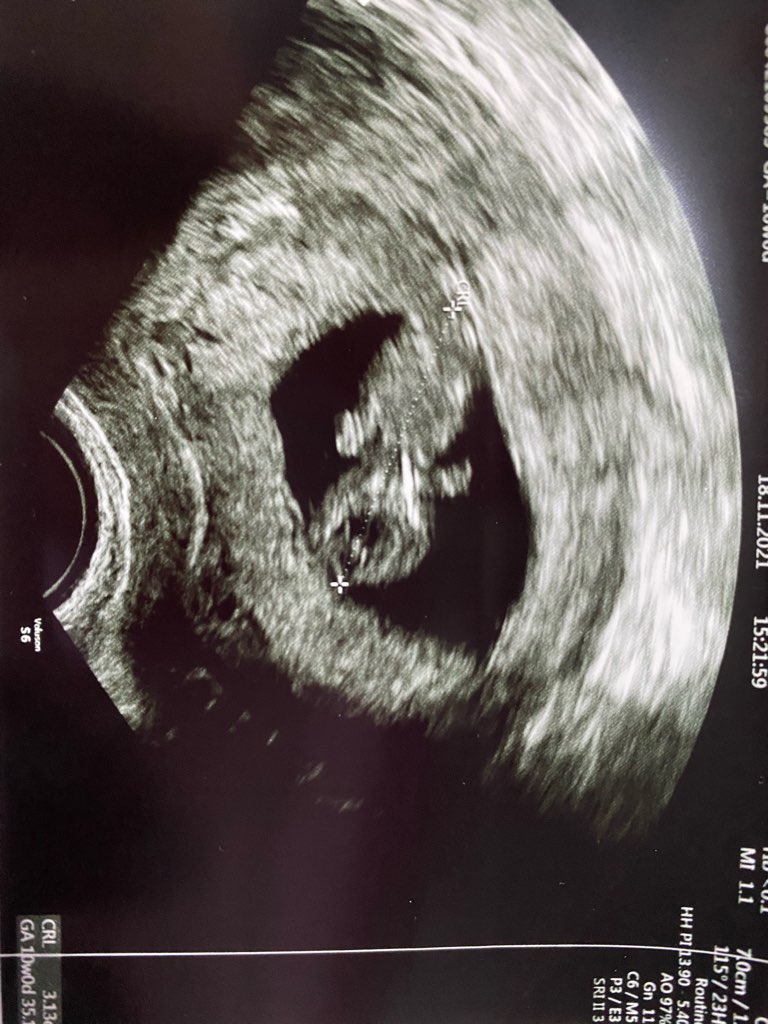

Jestem po i az ze szczęścia nie wiem co mam począć. Dzidziol na 3,13 cm. Puls 168. Wyniki krew mocz wszystko super jedyna notatka to nadplytkowosc.

Z USG 10+0 z om 10+1. Zaraz oszaleję z nadpobudliwości.

Aaaa i jeszcze dobra wiadomość krwiak się wchłania i jest mniejszy ❤️❤️❤️❤️ mam nadzieję że to już z górki.